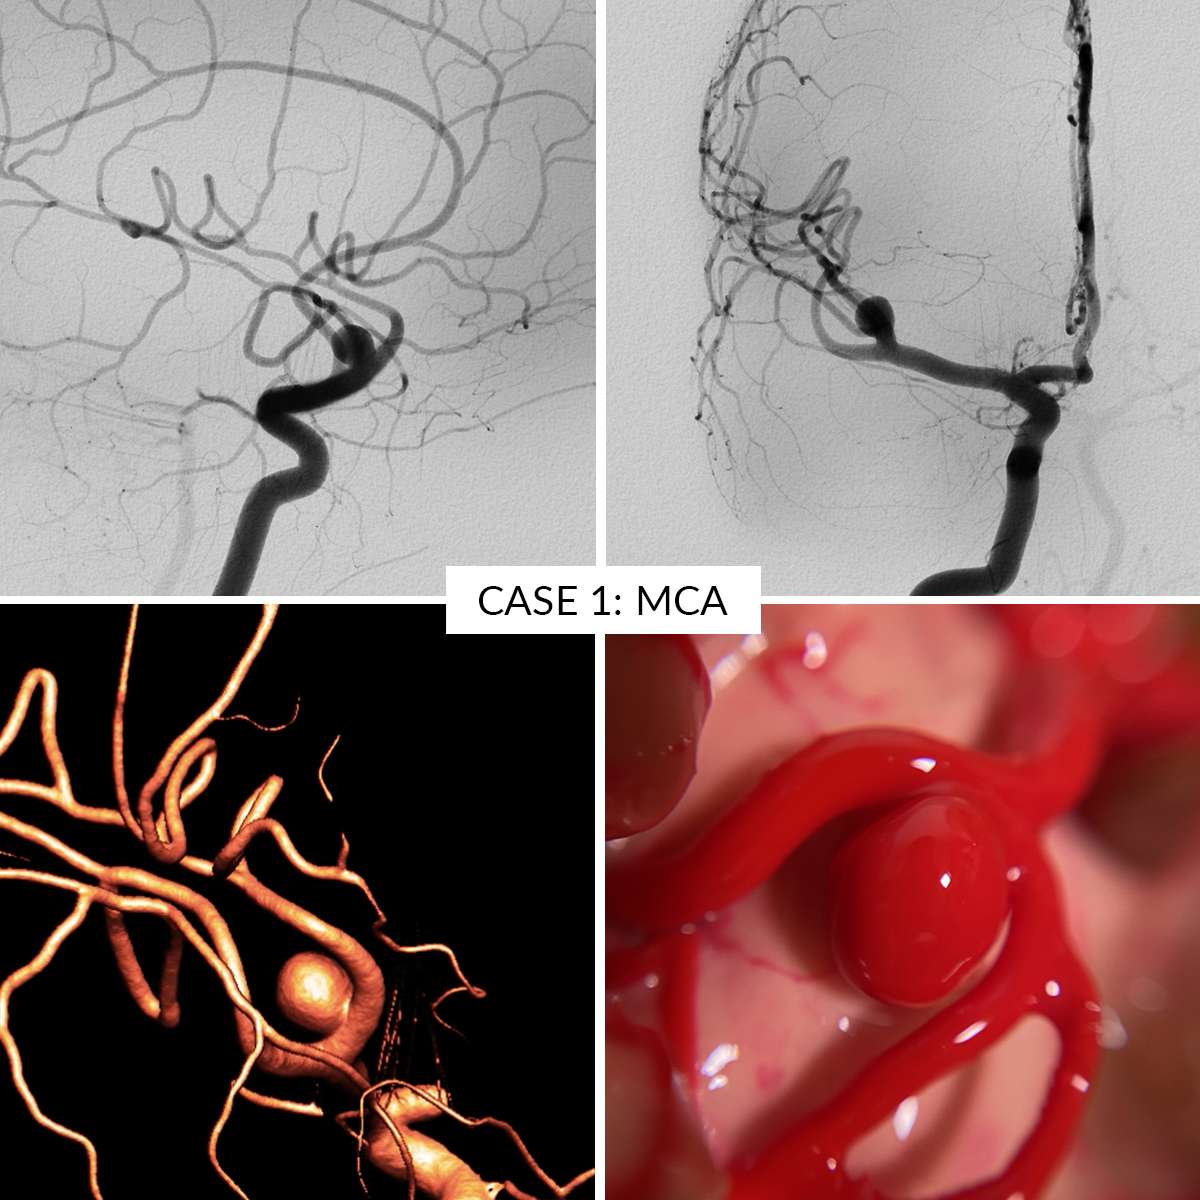

Case 1 : Middle Cerebral Artery

In the AneurysmBox simulator you can operate 5 different aneurysm cases:

- Case 1: Middle Cerebral Artery

Aneurysms are clippable unlimited number of times. Remove the clips gently to avoid damaging the aneurysms.